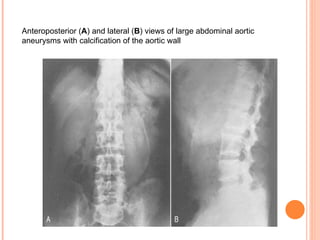

ABDOMINAL X RAY Abnormalities seen in 2/3 to ¾ of cases But AXR rarely ordered for AAA Retrospectively apparent in 90% Most common signs are wall calcifications and a paravertebral soft tissue mass, both seen in 65% Other signs include loss of psoas or renal outlines, renal displacement, and occasionally a properitoneal flank stripe AXR cannot be used to rule out an AAA

Anteroposterior  ( A )  and lateral  ( B )  views of large abdominal aortic aneurysms with calcification of the aortic wall

Anteroposterior (A ) and lateral ( B ) views of large abdominal aortic aneurysms with calcification of the aortic wall